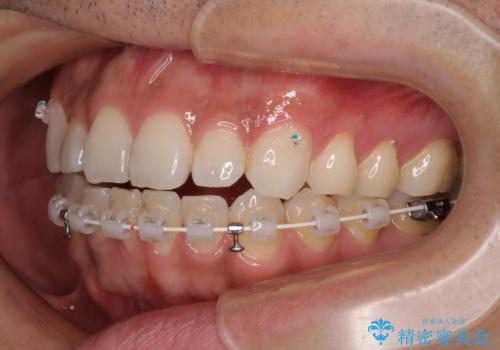

目立たない装置でデコボコを改善 ハーフリンガルによる矯正治療

- 30代男性

- 矯正装置

- ハーフリンガル

- 治療期間

- 1年4ヶ月

- 上下顎歯列のデコボコを改善したいとのことで来院された患者様です。

自己管理の大変なインビザラインや、目立つ表側のワイヤー矯正は避けたいとのことで、

上顎だけ裏側装置のハーフリンガルにて矯正しました。

一年と数か月で矯正を終えることができました。

下顎前歯部には後戻り防止のワイヤーを装着しています。